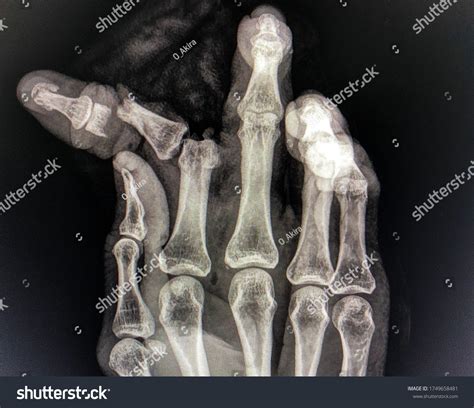

Diagnosing a Broken Index Finger

Diagnosing a broken index finger typically involves a physical examination and imaging tests. Your healthcare provider will:

• Examine the injured finger to assess the extent of the damage.

• Order X-rays to visualize the bone and determine the type and severity of the fracture.

• In some cases, additional imaging tests such as CT scans or MRIs may be required for a more detailed view.

Based on the findings, your healthcare provider will recommend the appropriate treatment plan.